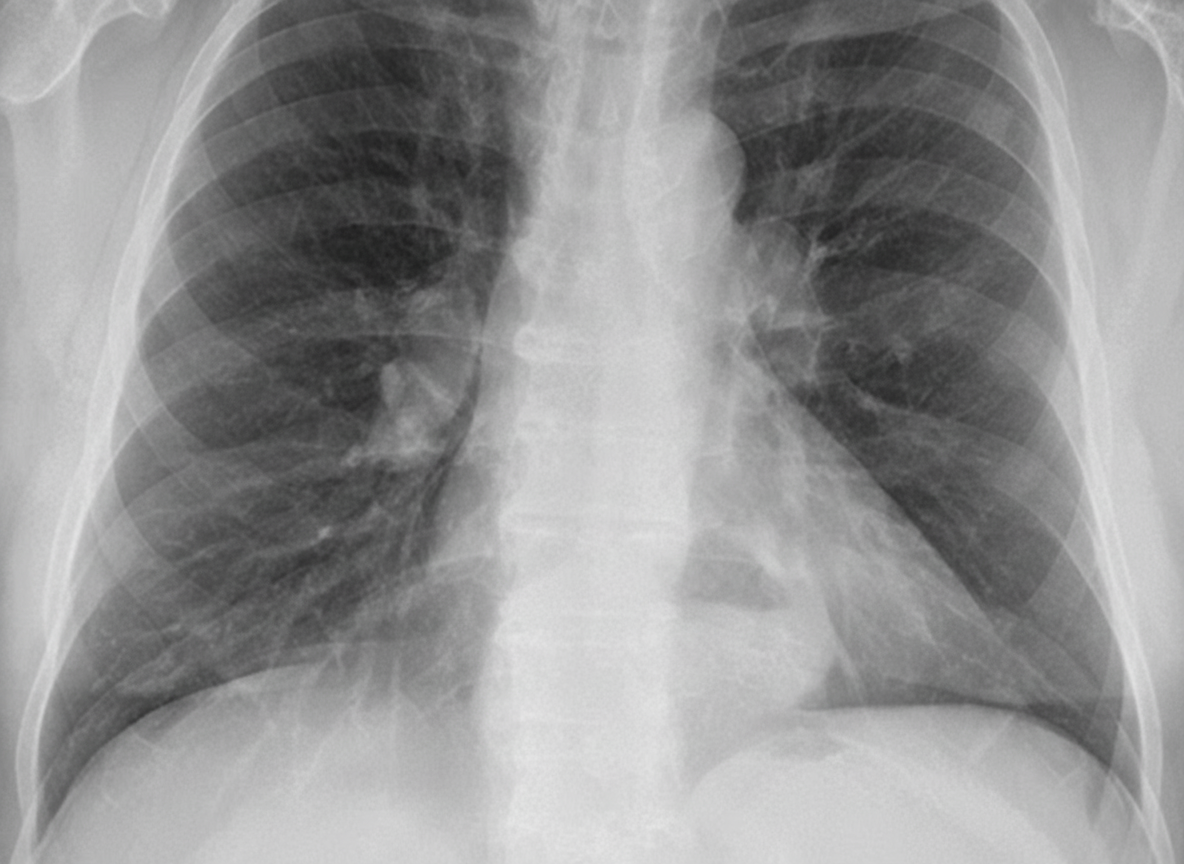

A 64-year-old woman with a longstanding diagnosis of mixed connective tissue disorder and pulmonary fibrosis is admitted with symptoms of recent increase in postprandrial retrosternal distress, heartburn, and nocturnal cough. Her ECG shows nonspecific T-wave changes and she finds minimal relief of her symptoms with sublingual NTG. On examination, she is not in any acute distress and is afebrile. Chest exam reveals bilateral crackles. CXR is shown. What is the most likely cause of this patient's acute symptoms?

Explanation: ***Large hiatal hernia*** - **MCTD** commonly causes **esophageal dysmotility** and **gastroesophageal reflux**, leading to large hiatal hernias with **retrocardiac air-fluid levels** on CXR. - **Postprandial retrosternal distress**, **heartburn**, and **nocturnal cough** are classic **GERD symptoms**, with minimal relief from **NTG** ruling out cardiac etiology. *Mediastinal abscess* - Would present with **high fever**, **sepsis**, and systemic toxicity, which are absent in this afebrile patient. - CXR would show **mediastinal widening** with **fluid collections**, not the typical **retrocardiac air-fluid level** seen with hiatal hernia. *Pneumopericardium* - Would present with **chest pain** and potentially **pericardial friction rub** on examination. - CXR would show **air around the heart** (**pneumopericardium sign**), not the **gastric air-fluid level** behind the heart. *Ileus* - Would present with **abdominal distension**, **nausea**, **vomiting**, and **absent bowel sounds**. - Symptoms are **abdominal**, not the **retrosternal** and **respiratory symptoms** described in this case.